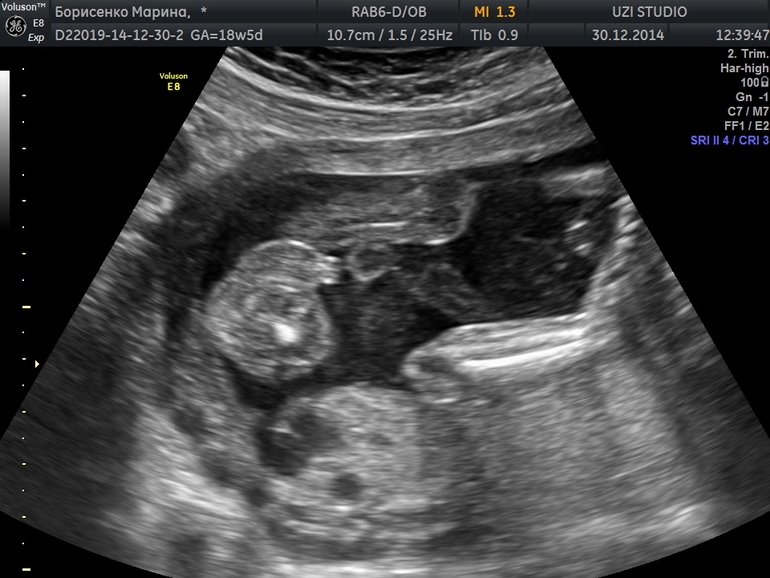

На верхней фотке из инета изображение, на нижней наше :)))